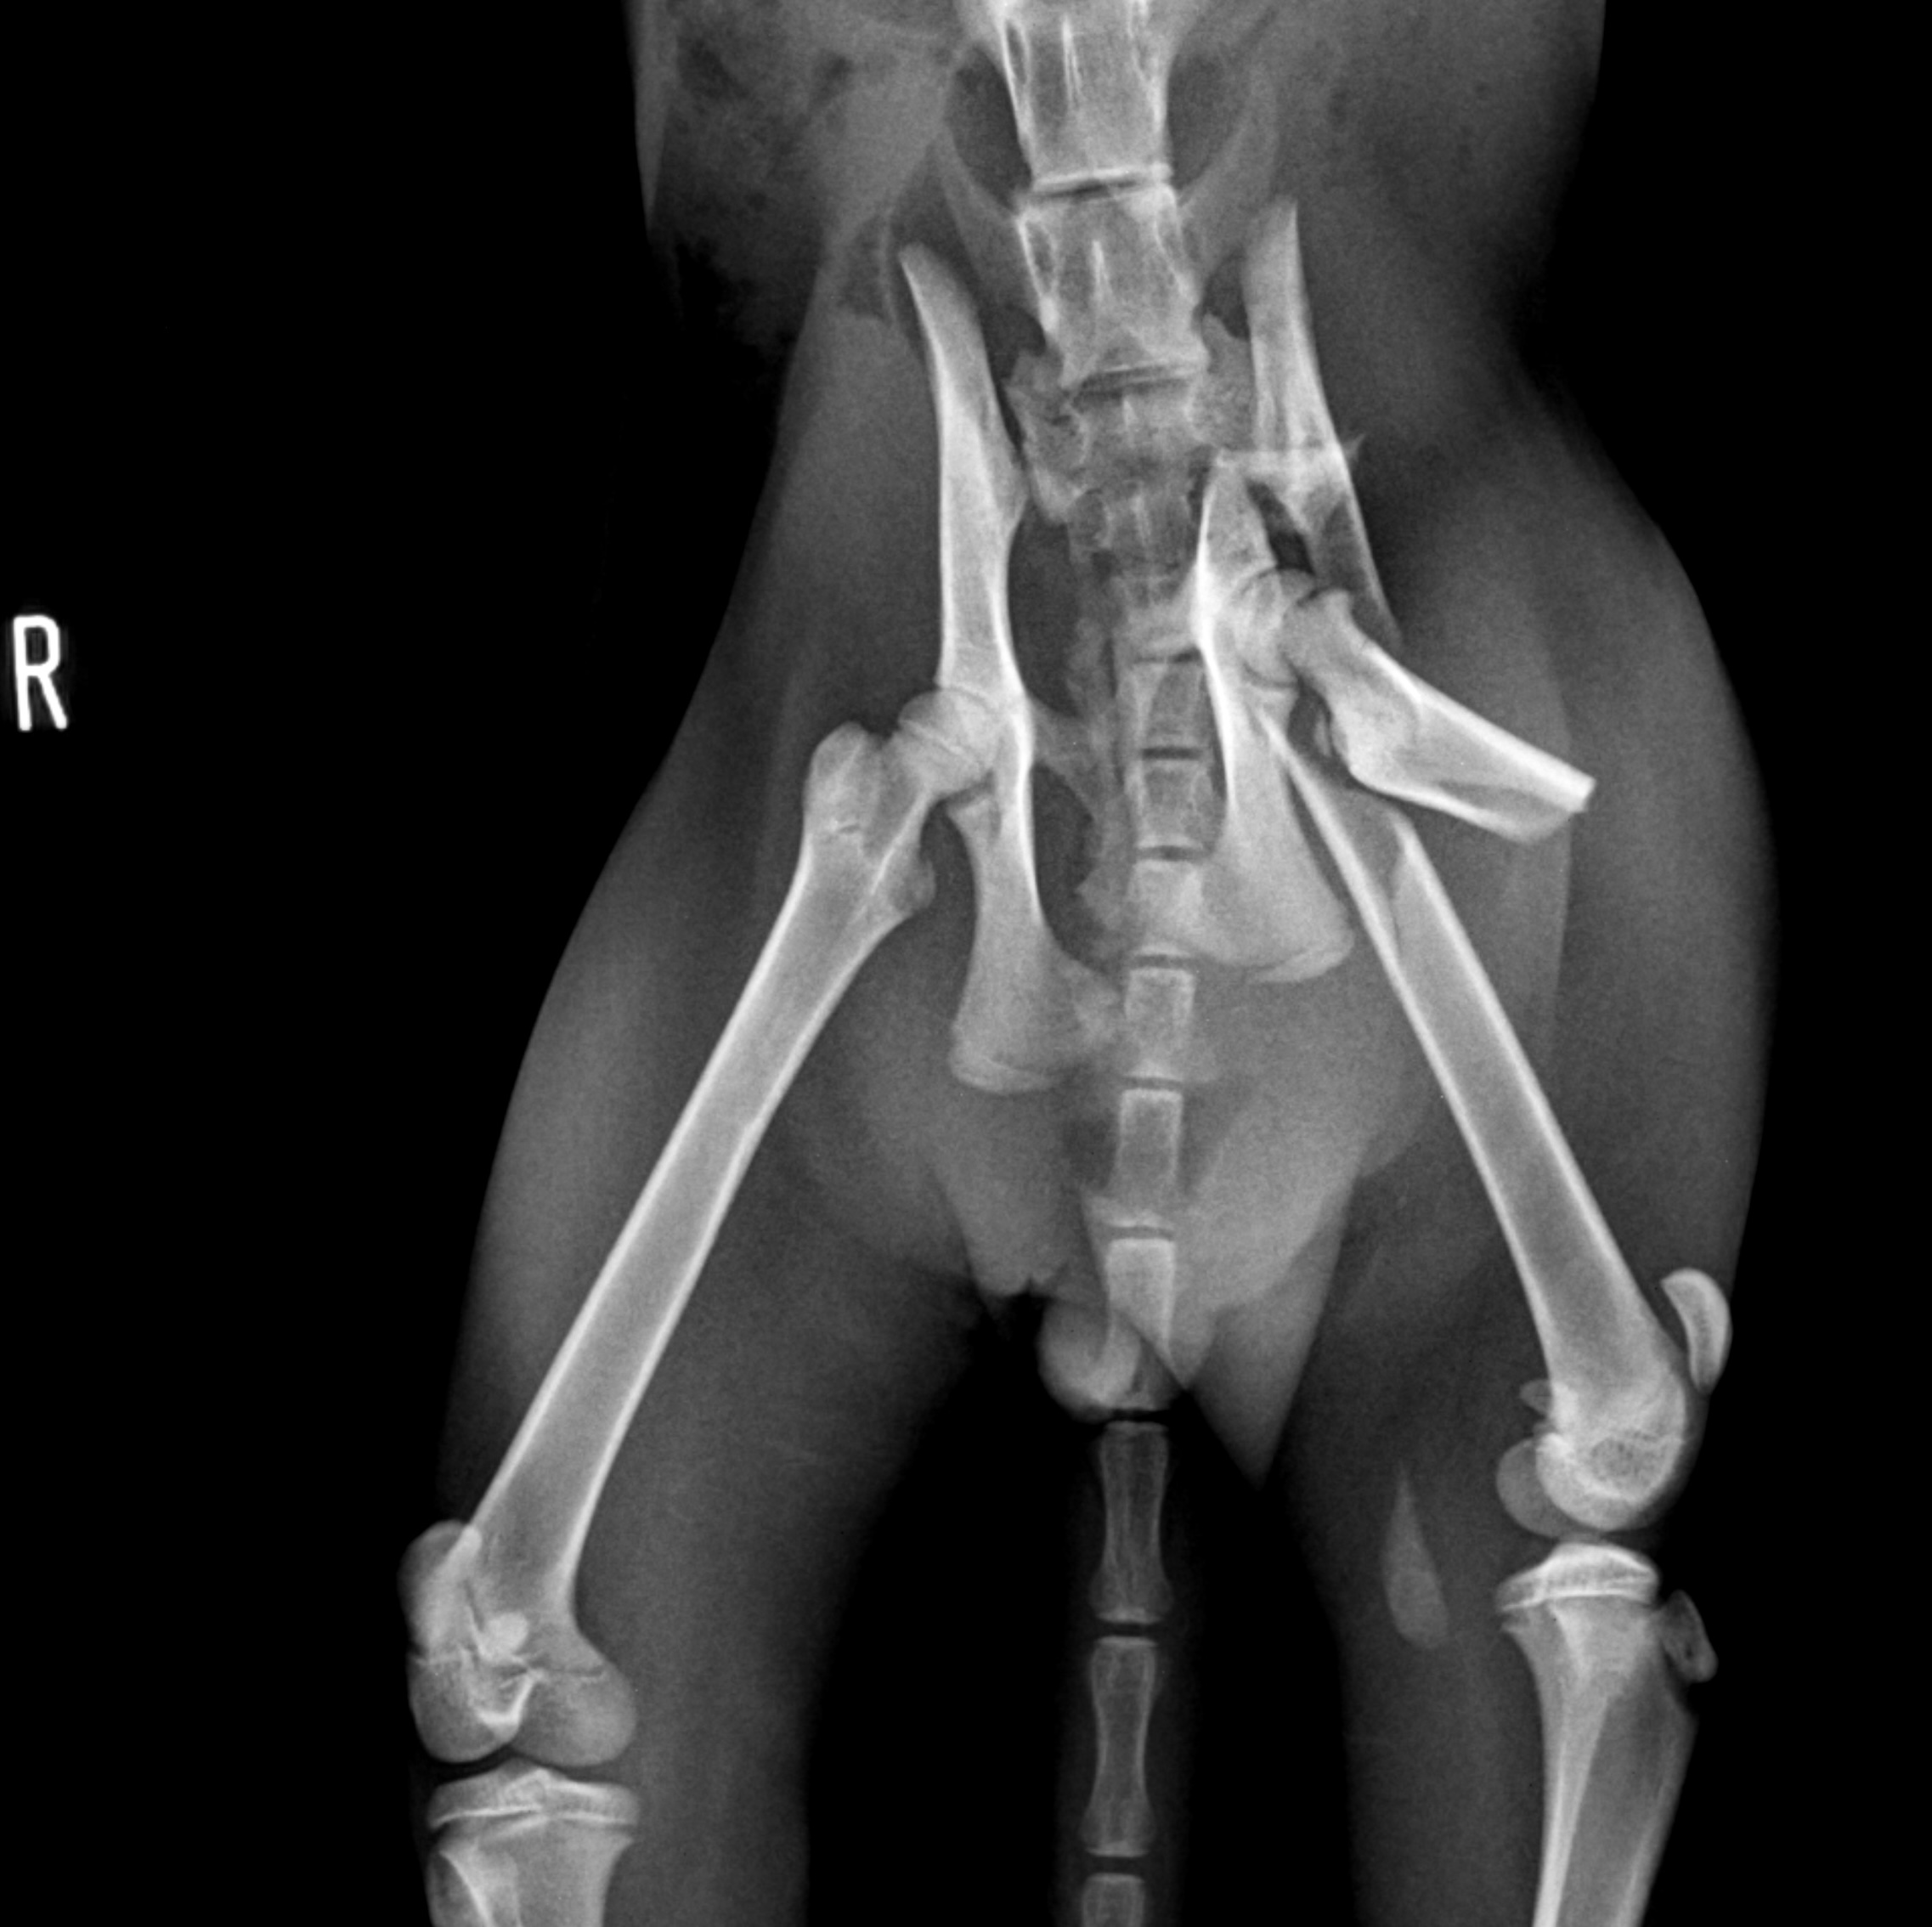

最近は屋内で飼育されている猫が増えてきたせいか交通事故に合う猫も少なくなったなぁ・・なんて思っていたら久しぶりになかなか激しい症例が来院しました。これだけ激しい骨折にも関わらず血液検査はオールクリア。早速手術に取り掛かることにしました。ただでさえデリケートな手技を行わねばならない骨盤骨折は、骨折している部位に到達するにあたり正常な部位にも骨切りをしてアプローチしなくてはならないのでなかなかスタミナと忍耐力が必要な手術です。今回は大腿骨も骨折していたのでまずはアプローチしやすい大腿骨をロッキングプレートで固定、続いて骨盤骨折整復という流れで手術を行いました。正味3時間の手術でしたが術後2日目には立って食事を食べられるようになりました。骨盤という骨はなかなか形態が複雑で整復するのに苦労しますが、歩けるようになって退院する姿を見ると疲れも吹っ飛んでいきますね。